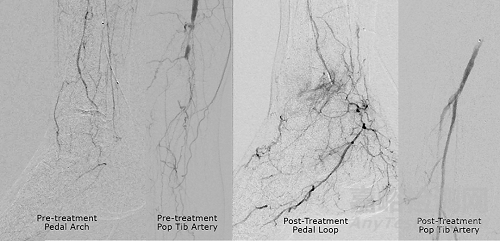

成功穿越脛骨慢性完全閉塞 圖片來源:Transit Scientific官網(wǎng)